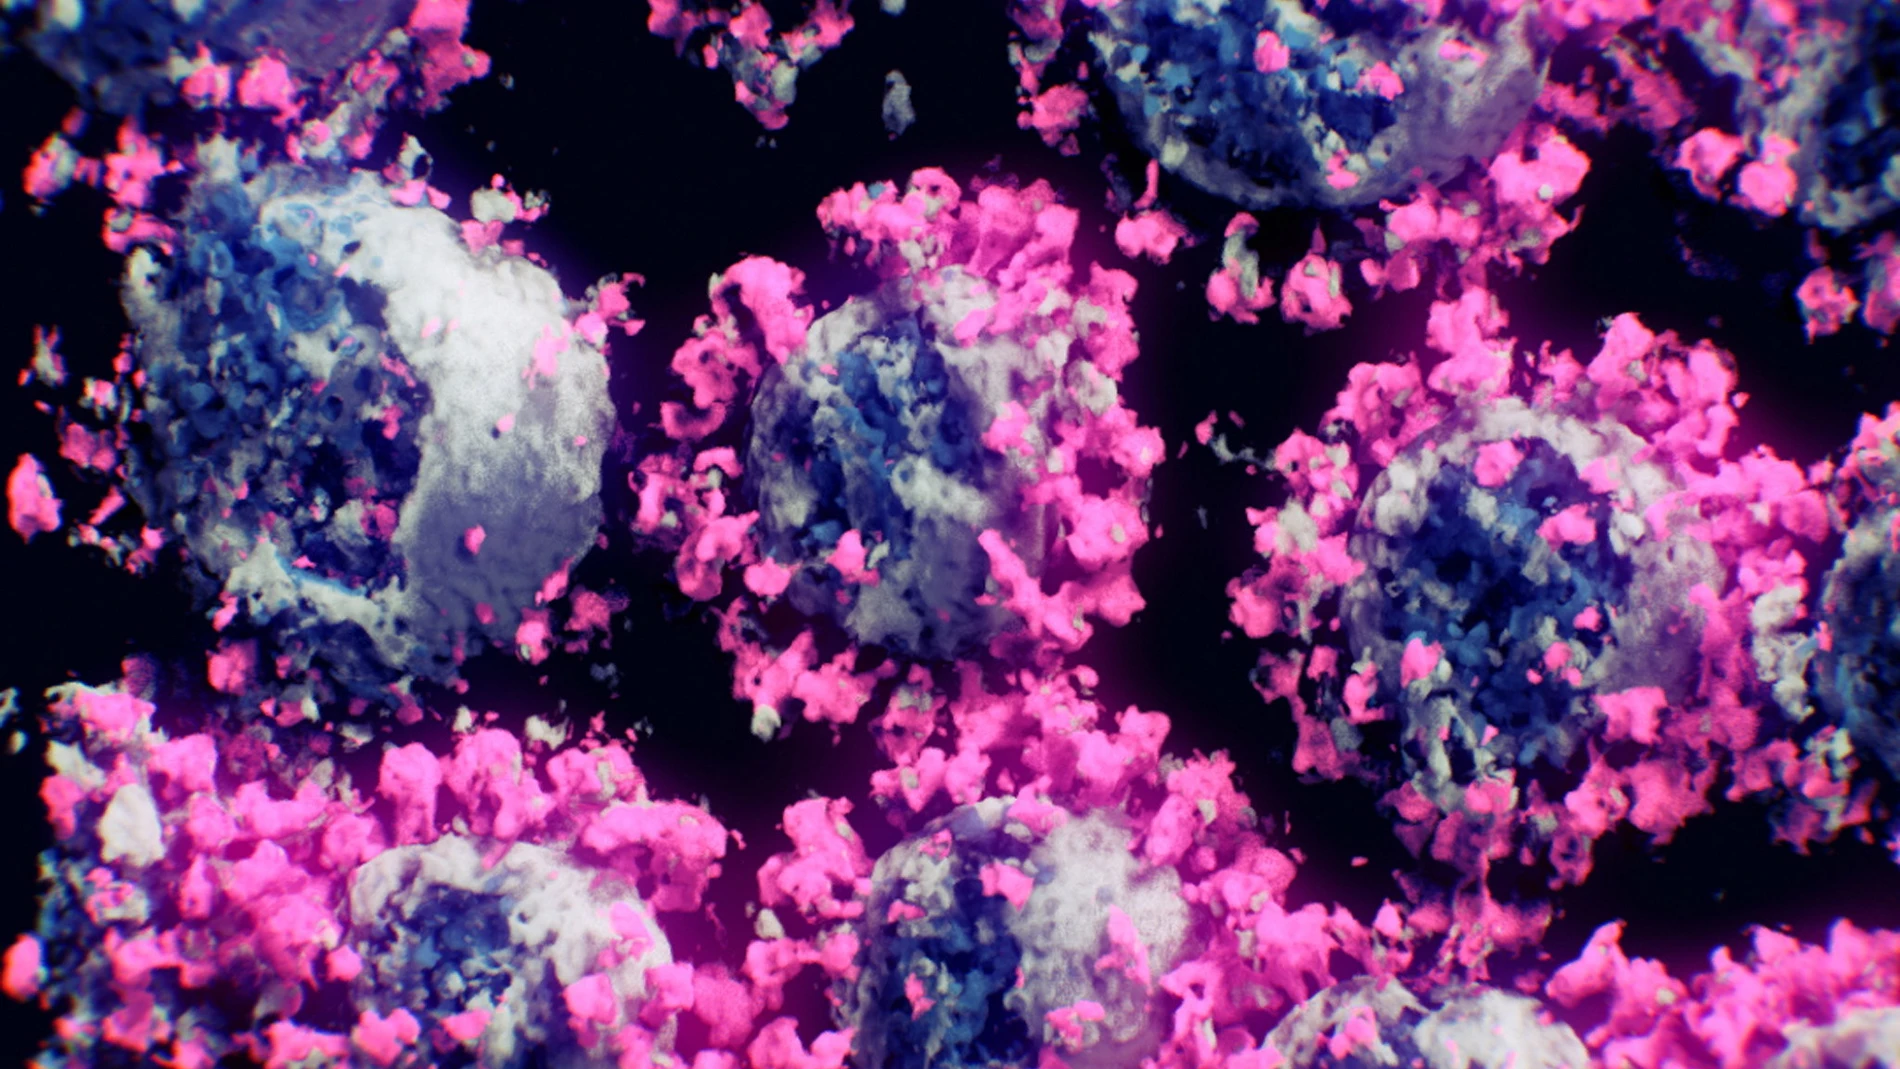

El nuevo coronavirus SARS-CoV-2, responsable de la pandemia de covid-19, es un miembro de una familia con 45 especies y decenas de variedades entre ellas. Los virus cambian constantemente debido a mutaciones, algunas persisten en el tiempo y otras desaparecen. Cada una de ellas tiene sus particularidades y comprenderlas es fundamental para anticiparse a los posibles impactos en la salud global. ¿Qué se sabe hasta la fecha? ¿Cómo se contagian? ¿Cuáles son las variantes más infecciosas y por qué? Esto es lo que la comunidad científica sabe hasta la fecha.

El primer paso en la infección por coronavirus es que el virus ingrese a las células. Para ello, las proteínas de pico –que le dan su forma de corona– en el exterior del virus SARS deben reposicionarse. Los científicos conocen la posición de los estados «inactivo» y «activo» de las proteínas de pico de los virus SARS-CoV-1 (responsable del brote asiático en 2003) y el SARS-CoV- -2, el problema es cómo se mueven de una posición a otra. Recientemente un equipo de científicos, liderados por Mahmoud Moradi, descubrió que ambos virus tienen formas completamente diferentes de cambiar sus proteínas de pico y en diferentes escalas de tiempo. El SARS-CoV-1 se mueve más rápido, se activa y desactiva, lo que no le da tanto tiempo para adherirse a las células porque no es tan estable. El SARS-CoV-2, por otro lado, es estable y está preparado para invadir la célula. El equipo de Moradi también descubrió que hay una región en el extremo de la proteína de pico que se ha ignorado pero que es fundamental para la estabilidad de la proteína. Las mutaciones en esa región podrían afectar la capacidad de transmisión y esto permitiría diseñar terapias que alteren la dinámica y hagan que el estado inactivo dure mucho más tiempo.